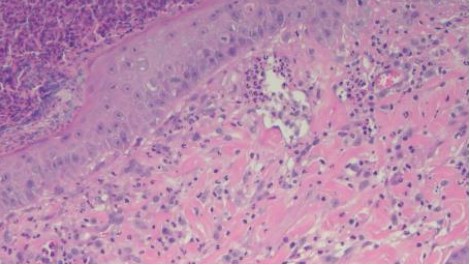

組織病理結果為化膿性嗜酸球性真皮炎,如圖四所示。排除感染的問題,提高prednisolone劑量到3mg/kg sid,兩週後硬皮病灶消失、搔癢症狀緩解,開始逐漸減量類固醇,目前1mg/kg qod狀況良好如圖五所示,持續治療。

A B

C D

圖四:A, 檢體為表皮層到真皮層組織,少部分表層皮下脂肪有涵蓋在檢體內。B, 表皮結構完整,表面有大量的壞死細胞碎片、片狀角質、脫落的角化細胞覆蓋或是形成沒有破裂的膿皰結構,皮膚糜爛但局限於表皮,基底膜完整。C, 真皮層輕微水腫,有少量到中等量、零散分布的發炎細胞浸潤,細胞有略微分布表層真皮或是毛囊腺體周圍的傾向,但不明顯。D, 浸潤的細胞以嗜中性球、嗜酸性球以及肥大細胞為主,血管內也可見到數量明顯增加的嗜中性球及嗜酸性球,皆為分化成熟沒有惡性特徵。D, 表皮層中有見到一顆凋亡細胞 (apoptotic cell),但周邊沒有淋巴細胞包圍。E, 此外毛囊腺體的結構完整,沒有破裂,毛囊內也沒有見到細菌、黴菌或是寄生蟲。以特殊染色B&B檢查檢體,沒有見到細菌病原。